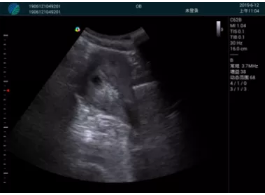

清晰顯示孕囊,通過軟件包計算孕齡7w+6d

M20實時引導(dǎo),術(shù)中清晰顯示孕囊被破壞和抽吸針的過程,清晰顯示吸引針

抽吸結(jié)束后縱切子宮,孕囊已被完全抽吸,未見明顯殘留

橫切子宮,發(fā)現(xiàn)右側(cè)宮腔靠近宮角處有少許脫模樣殘留

M20引導(dǎo)下,抽吸針找到右側(cè)宮角處再次清掃

二次抽吸后再次進行超聲檢查,宮腔未見殘留,宮腔線清晰顯示

超聲引導(dǎo)下可視化人流是技術(shù)安全性的保障,一般對人流術(shù)設(shè)備預(yù)算不高,M20具備婦產(chǎn)科軟件包,且穿透力圖像質(zhì)量好,既滿足人流引導(dǎo)需要,也可用于床旁超聲的需求。